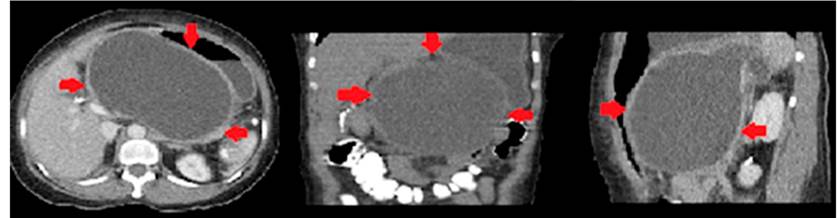

Al examen físico de ingreso en nuestra institución presenta abdomen distendido, dolor y masa palpable en el epigastrio, sin ictericia. Los paraclínicos mostraron hemograma sin leucocitosis, hiponatremia, hipocloremia e hipopotasemia leves, no acidemia metabólica, lactato levemente aumentado e hiperbilirrubinemia leve, a expensas de la directa con amilasemia leve. Se consideró una posible pancreatitis aguda. Ante esta situación se decidió realizar una tomografía computarizada de abdomen contrastado, que reportó pseudoquiste de 1460 mL de volumen aproximado, en contacto con la pared gástrica posterior (Figura 1).

Figura 1 Tomografía computarizada de abdomen y pelvis. Presencia de pseudoquiste pancreático de 16 x 16 x 11 cm, sin líquido libre en la cavidad.